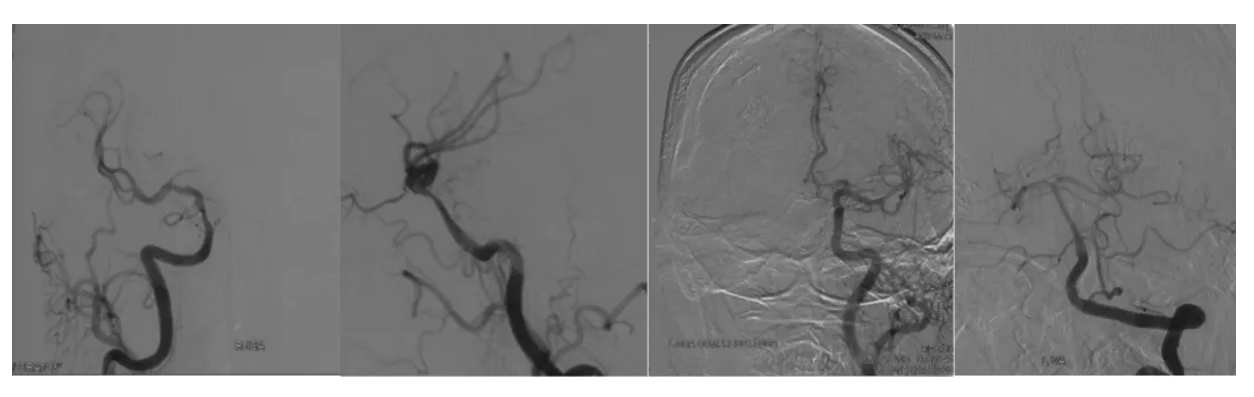

3. Cerebral angiography showed that the right internal carotid artery was unevenly narrowed at the bed-surge segment and the upper end of the bed-surge, displaced medially and superiorly, with the posterior and anterior communications not open, and the middle cerebral artery blood-supplying region had a lesser distribution of blood vessels; the vertebral basilar artery did not have an obvious cortical anastomosis supplying blood to the right cerebral hemisphere; and the left anterior cerebral artery was double-trunked.

The right saddle region was occupied and recurred many times, also treated by Gamma Knifewith residual regrowth of the tumor. Preoperatively, the right motor nerve was completely paralyzed and had poor vision, but the left limb movement was not affected. Previous pathology had confirmed the diagnosis of malignant meningioma. Taking the above considerations into account, the indications for surgery were clear. How to resect the tumor as much as possible and at the same time protect the blood supply of the branches of the internal carotid artery and the perforating blood vessels was the key to the surgery. The patient had undergone multiple surgeries and radiation treatments in the past, and the tumor was generally hard and tough with severe adhesions, which made it difficult to resect the tumor while protecting the blood vessels. Cerebral angiography showed poor blood supply in the region of the right middle cerebral artery and no good blood supply compensation. Therefore, ensuring the blood supply of the right internal carotid artery is the key to preventing postoperative cerebral infarction, guaranteeing limb survival, and removing the tumor as much as possible. Given that the patient's right superficial temporal artery has been destroyed in many operations, low-flow bypass is not good to realize. Therefore, we considered choosing the radial artery as the bridging vessel to perform high-flow bypass with anastomosis between the internal carotid artery and the middle cerebral artery. While resecting the tumor as much as possible, it is also necessary to protect the internal carotid artery, the anterior cerebral artery and the middle cerebral artery to avoid deep brain infarction. The residual tumor will be treated with adjuvant therapy at a later stage to control the growth.